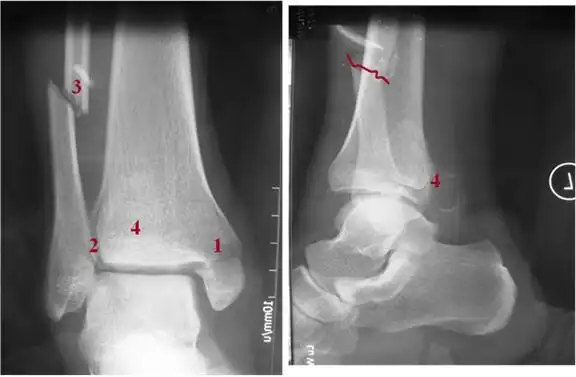

三踝骨折日记术前拍片